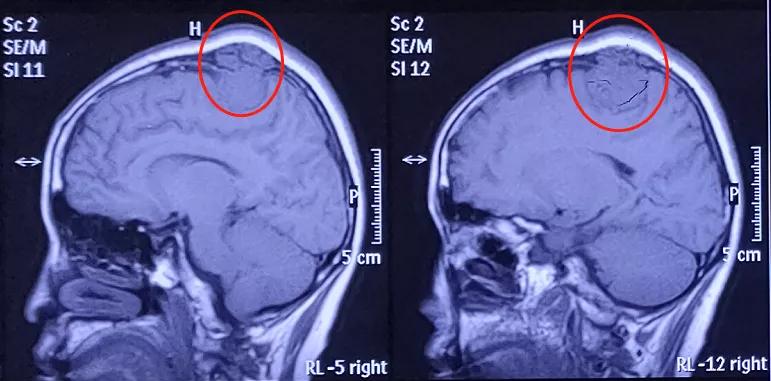

患者拍了核磁共振后,发现她颅内有一枚较大的脑膜瘤,且脑膜瘤穿通颅骨,在头皮下增长。这种情况,贾主任建议进行手术切除。

就像这例病例,有一些脑膜瘤,它侵蚀骨质,是侵袭性脑膜瘤。虽然我们说脑膜瘤从病理上来说应该是良性的,但像这种侵袭骨质比较厉害,侵袭性比较强的,有可能是低度恶性的脑膜瘤。

所以对于这种侵袭骨质的脑膜瘤,做手术的时候需要把骨头也清掉,如果说侵蚀硬膜了,还要把硬膜清掉。这都是为了不残留,预防复发。但要是因为某种情况的限制,血管、神经挨得太紧,或者没有清除干净侵蚀的骨质或硬膜等,肿瘤组织残留了,复发的可能性还是很大的。